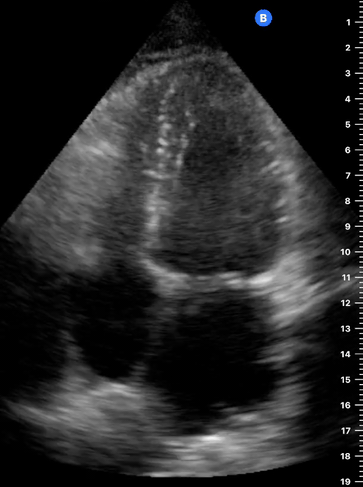

A4C

APICAL FOUR-CHAMBER VIEW

This view looks at the heart from the apex. When done properly, it achieves a horizontal cut of the heart that demonstrate all four chambers simultaneously. Consequently, its main utility is to assess the relationship between LV and RV. Beware, differentiating the chambers by ventricle size or thickness is not recommended, and it could lead to confusion in case of RV enlargement.

ORIENTATION & TECHNIQUE

Place the transducer at the apex beat and angle it towards the right scapula. The correct image results from sliding the probe until the interventricular septum is in the middle of the screen, vertically dividing both sides of the heart. If using a cardiac preset, the probe’s marker points towards the patient’s left arm. Simpler, in this view, the probe notch should meet the marking on the screen, which is fundamental to avoid confusion.